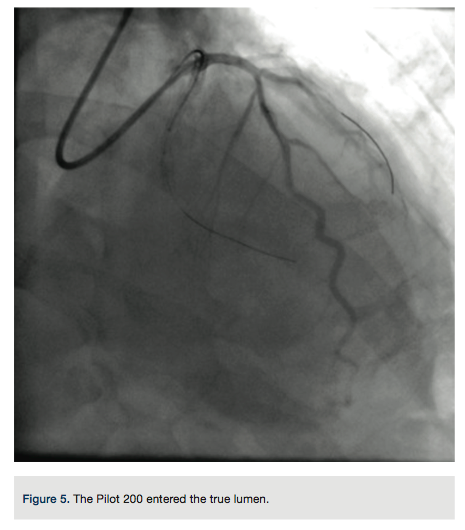

A Pilot 200 wire (Abbott Vascular) was loaded in a CrossBoss catheter (Boston Scientific) and advanced into the circumflex artery. The CrossBoss was slowly advanced, using the Pilot wire to redirect the device to remain as close to the lumen as possible. Once past the total obstruction, the Pilot 200 wire was used to re-enter the distal circumflex (Figures 3-4). A balloon dilation with a 1.5 mm x 20 mm long balloon was performed at 12 atmospheres (atm) followed by a 2.5 mm x 20mm balloon at 12 atm. A Runthrough wire (Terumo) was placed in the first marginal and stenting of the circumflex was performed using a 2.5 mm x 38 mm Promus Premier stent (Boston Scientific) overlapped with a 3.0 mm x 24 mm Promus Premier stent. High-pressure inflation in the entire stented segment was performed using a 3.0 mm balloon. The segment proximal to the first obtuse marginal was dilated to high pressure using a 3.25 mm balloon (Figures 5-7). A good angiographic result was seen (Figure 8).